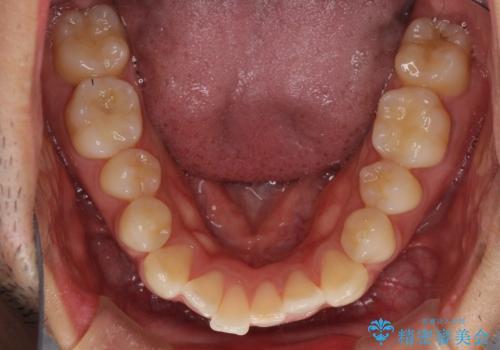

- 前歯のデコボコを治したいとのことで来院された患者様です。

上下顎ともに歯列全体の後方移動とIPR(歯と歯の間を削る)によってデコボコが解消するように設計し、インビザラインにより治療を行うこととしました。

毎日22時間以上しっかりとマウスピースを装着していただいたので、スムーズに治療が進みました。歯と歯の間を削ることでうまくスペースコントロールでき、1年強で終えることができました。